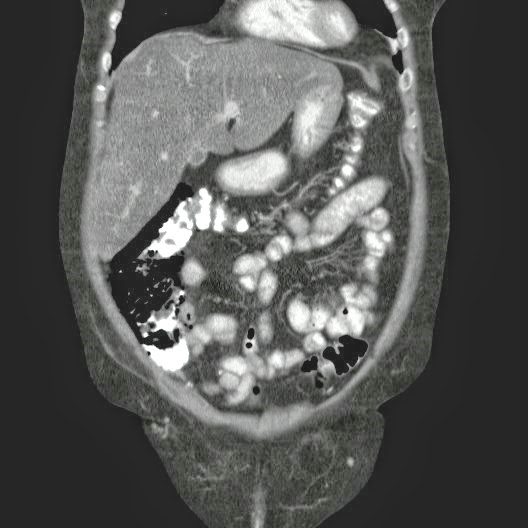

Paciente con antecedente de ALIF (Fusión lumbar intersomática anterior) 360 grados L5-S1 hace siete meses, quién presenta herida de abordaje anterior con dehiscencia de sutura, con cierre por segunda intención, quien consulta por cuadro clínico de dos días de secreción purulenta en herida quirúrgica, niega fiebre, niega otras sintomatología, refiere episodios previos similares.

Paciente en POP de ALIF L5-S1 quien presento dehiscencia de la herida abdominal con ISO superficial ya tratada, sin embargo persiste con dehiscencia y desde ayer con supuración asociado a fiebre subjetiva. Se realiza eco abdominal con colección en pared sugestiva de absceso, elevación de RFA por lo cual se considera se debe hospitalizar para manejo antibiótico, drenaje de la colección, manejo médico y vigilancia neurológica.

- ¿Hallazgos Escanografia?

2. Hay una colección de la pared abdominal en el flanco derecho, que realza en la periferia con el contraste, e intraabdominal tiene aire pero no me parece colección intraabdominal porque la grasa no está alterada.

3. Recomendado: Drs. JOSÉ M. ZUÑIGA A.1, FRANCO ORELLANA G.1, MARCELO CASTRO S.3, ROLANDO SEPÚLVEDA D.4, HORACIO RÍOS R.4, Int. VELIA SALDÍAS H.2. Neumatosis Intestinal: Caso Clínico-Radiológico. Pneumatosis intestinalis. A case report. Rev Chil Cir v.61 n.1 Santiago feb. 2009